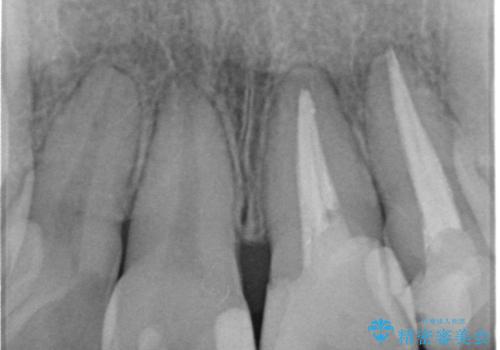

- 神経の死んでしまっている前歯の変色の改善を求めて来院されました。

根管治療をしたのち時間が経過して変色が目立つ歯と、レジン充填が複数箇所に及んでいる歯も同時にオールセラミック治療を行っていくこととなりました。